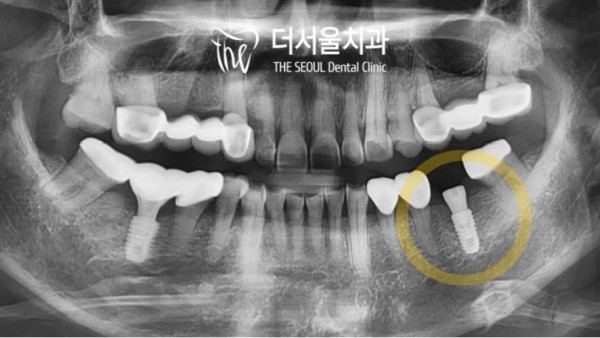

36번을 보시면 빈공간이 보이는데요.

35번과 37번을 지대치로 브리지를 하셨던 부분입니다.

다른 치아는 지대치였던만큼 치근이 남아있지만 36번은 아예 치아가

상실된지 오래된 공간이었습니다.

이렇게 오랜시간 치아를 상실한채로 빈공간으로 두게되면

치조골이 소실되어 임플란트를 심기 어려워질 수 있습니다.

If you look at number 36, you can see the empty space.

This is the part where you bridged 35 and 37 on the ground.

The other teeth have a root as much as it was a ground tooth, but number 36

It was a long-lost space.

If you leave your teeth empty after losing them for such a long time

The alveolar bone may be lost, making it difficult to plant an implant.